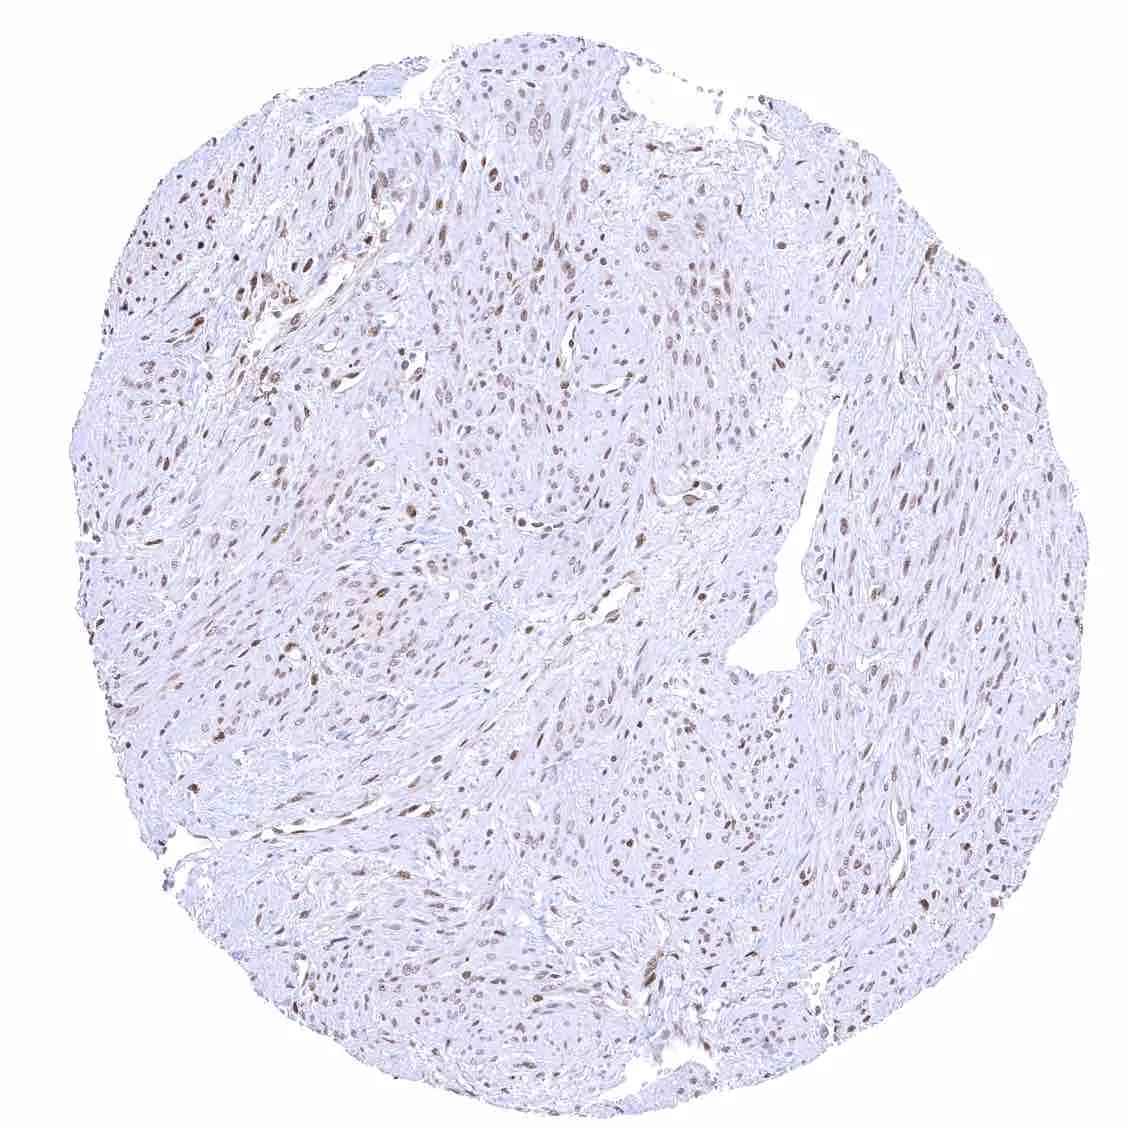

Aorta, media – Strong nuclear p27 staining of muscle cells in the aorta.